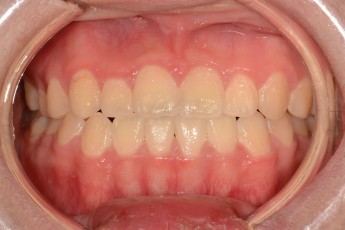

BEFORE & AFTER

- 덧니교정